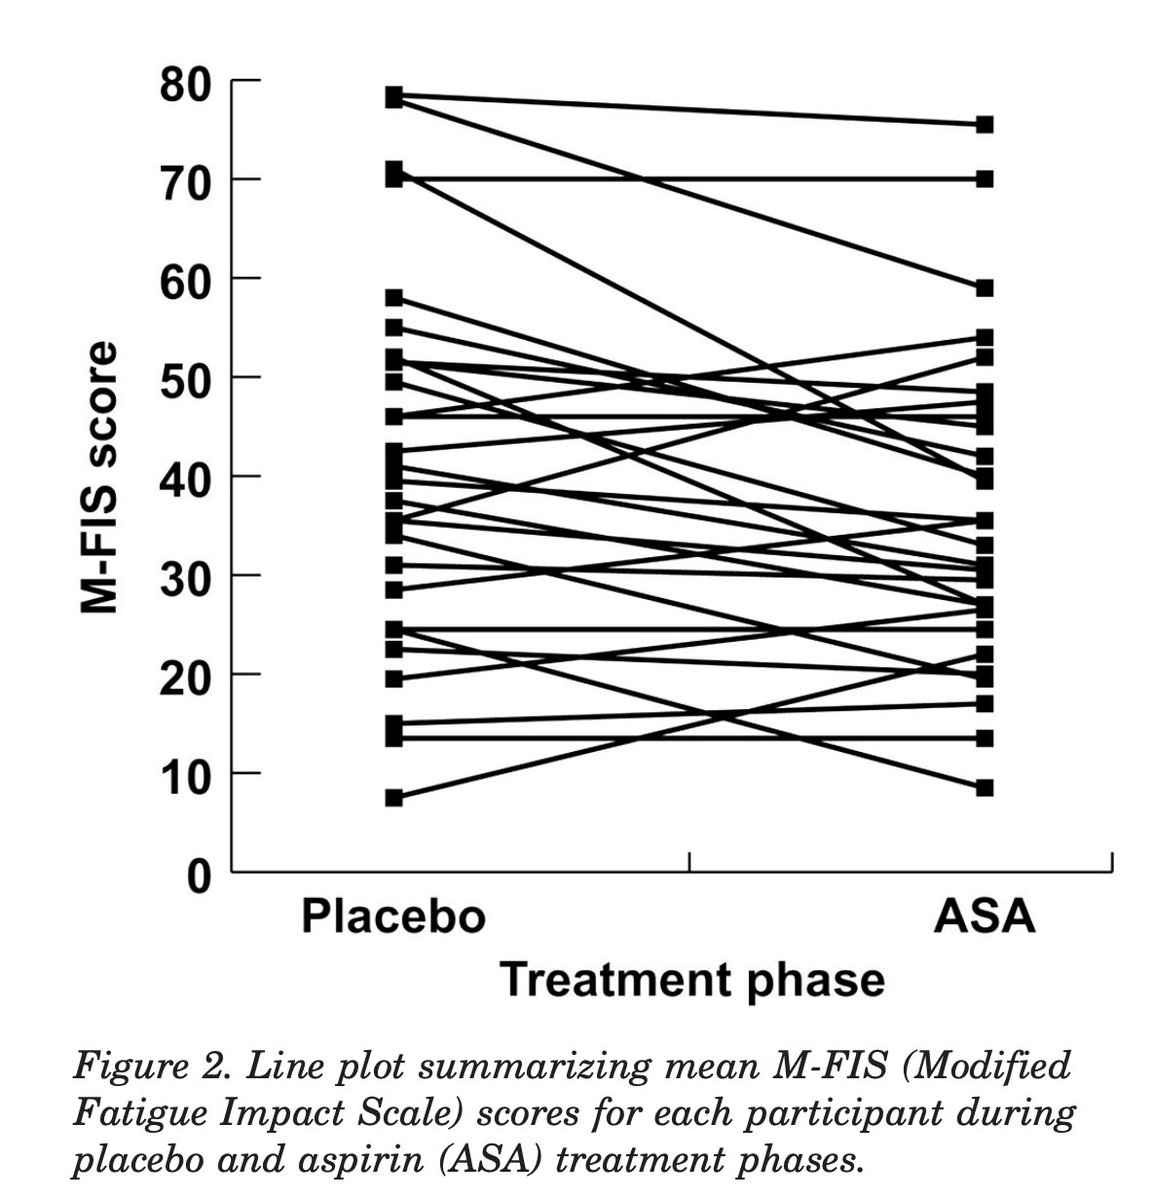

If you’re just generally tired, aspirin can be a good tool in the arsenal.

It’s been shown to counteract fatigue, and in my experience can perk you up if you’re just not feeling it.

It’s been shown to counteract fatigue, and in my experience can perk you up if you’re just not feeling it.